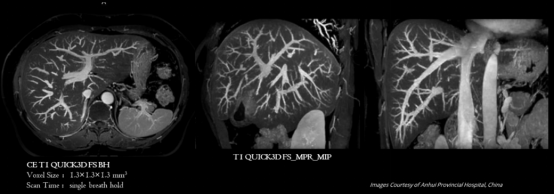

▼超高分辨腹部成像▼

可进行头部、腹部、膝关节、胰腺等部位的超高分辨扫描,应用于烟雾病、帕金森病、脑肠轴、心源性卒中、肌萎缩侧索硬化(渐冻症)等的临床研究,呈现更丰富的细微结构,更精准的定量分析,助力全身疾病超早期发现。

uMR Jupiter 5T提供高信噪比、分辨率、成像速度的同时,提供丰富的高级应用,满足全身各部位的临床应用。